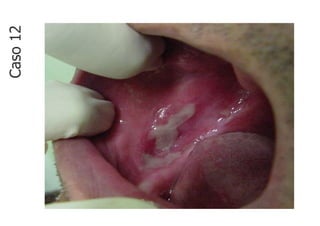

Caso

12

• Lesão fundamental: úlcera

• Localização: mucosa jugal

direita

• Quantidade: múltiplas

• Tamanho: 3 cm x 2 cm

• Borda: bem delimitada

• Cor: branca e avermelhada

• Em mucosa jugal direita nota-se lesão ulcerada,

esbranquiçada, única, situada em ápice lingual, bem

delimitada, com base séssil, com superfície lisa e que

mede aproximadamente 3,0 cm x 2,0 cm.

CASO 12 - Descrição